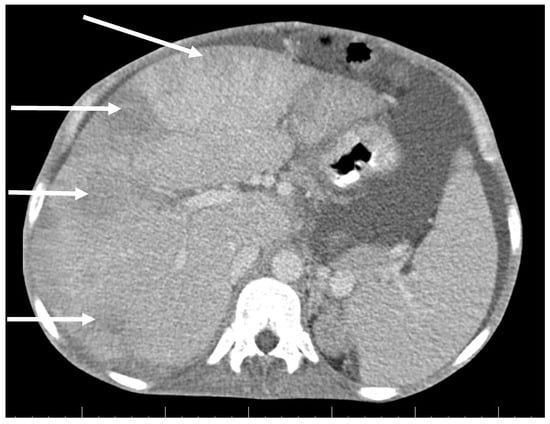

The diagnosis of metastatic ovarian cancer was assumed. Histology of a CT-guided fine-needle liver biopsy sample revealed fibroproliferative inflammation and chronic abscess with actinomycotic granules.

The radical surgery was postponed for two months until the patient´s nutritional status improved. Hysterectomy, bilateral salpingo-oophorectomy, appendectomy and adhesiolysis was performed. On the cut, the mass on the right ovary, with dimensions of 50 × 50 × 30 mm, showed yellowish tissue with necrosis. Histopathology showed that the mass consisted of confluent granulomas with purulent exudate containing fibrillar structures corresponding to actinomycotic granules despite two months of targeted antibiotic treatment (Figure 3).

Figure 3. Histopathology shows granuloma with purulent exudate and actinomycotic granules. Haematoxylin–eosin stain. (With kind permission of Dr. Kamila Benková, Department of Pathology, Hospital Na Bulovce.).